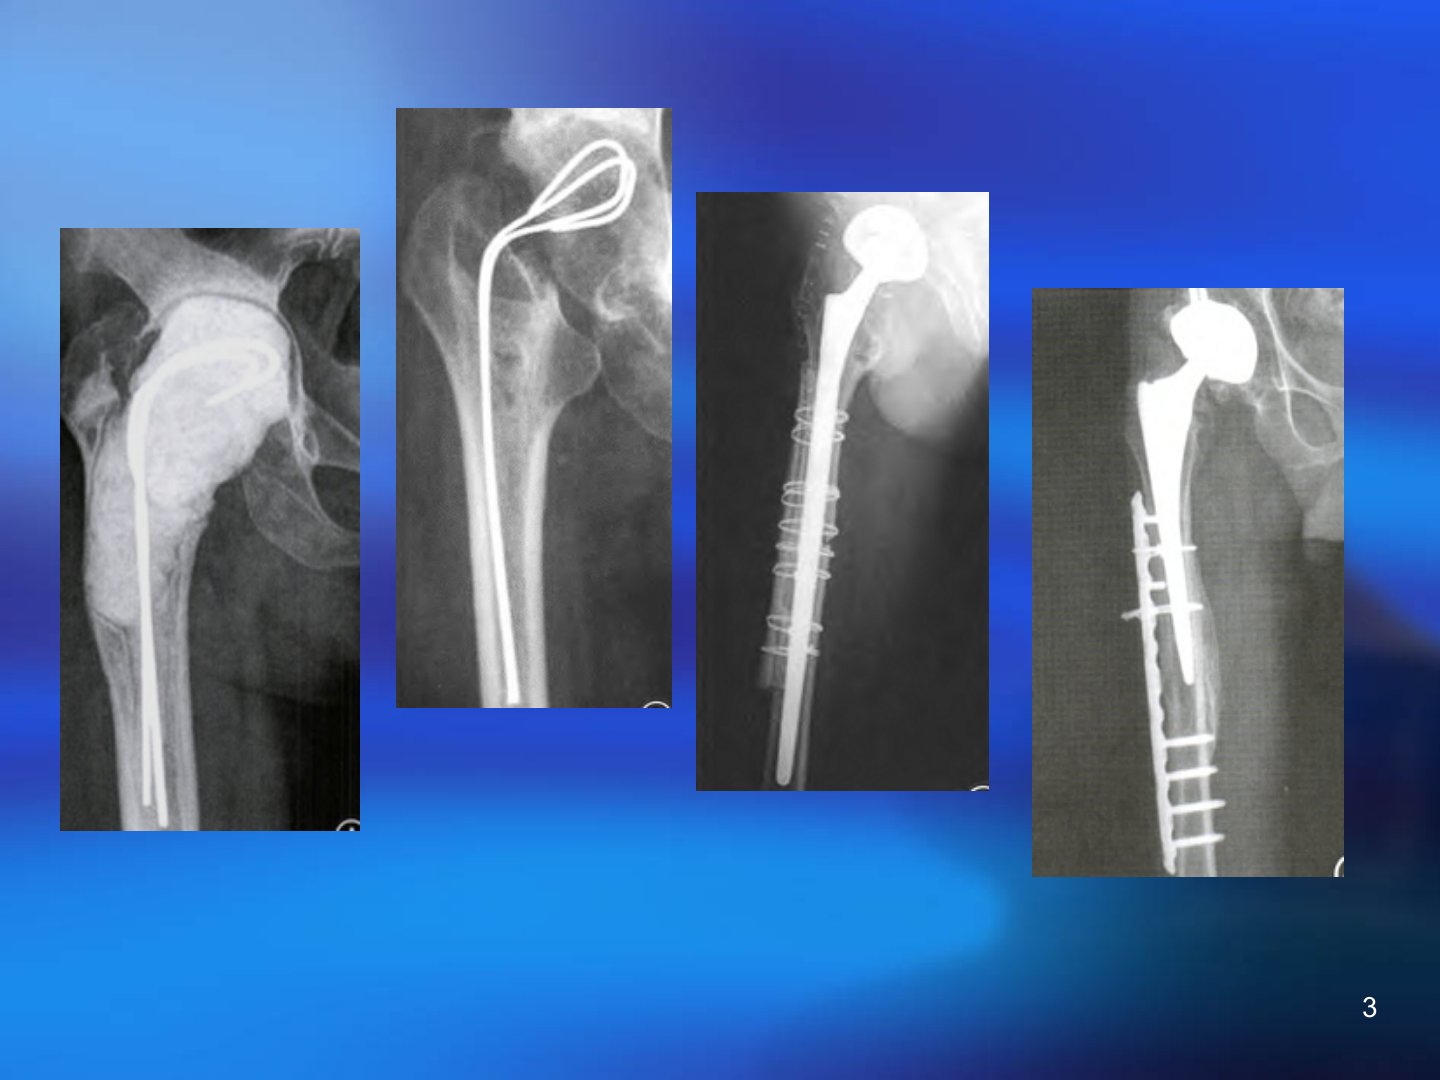

上海新华医院骨科王晖医生于2016年5月6日介绍髋关节置换术后股骨假体周围骨折(PFF)发生率逐年上升20052030年髋关节翻修需求增长约167翻修原因包括关节不稳、脱位、假体松动、感染及PFF等。PFF危害大具有高死亡率、高不愈合率、高再手术率等特点。其发病机制涉及外伤、骨皮质缺损、假体松动等因素确切发病率难以统计文献报道从01到18不等。分型系统多样其中Vancouver分型最受认可。处理方面非手术治疗适应症少仅适用于特定情况且并发症多。手术治疗除无移位、假体稳定的A型骨折外均建议手术适应症包括假体松动、骨折明显成角畸形等。手术方法包括髓内固定、假体翻修、髓外固定等需根据骨折类型、假体稳定性及宿主骨情况合理选择。治疗目标是骨折愈合、假体稳定、恢复功能。一般原则为移位骨折需固定松动假体需翻修有明显骨量丢失的要进行植骨。